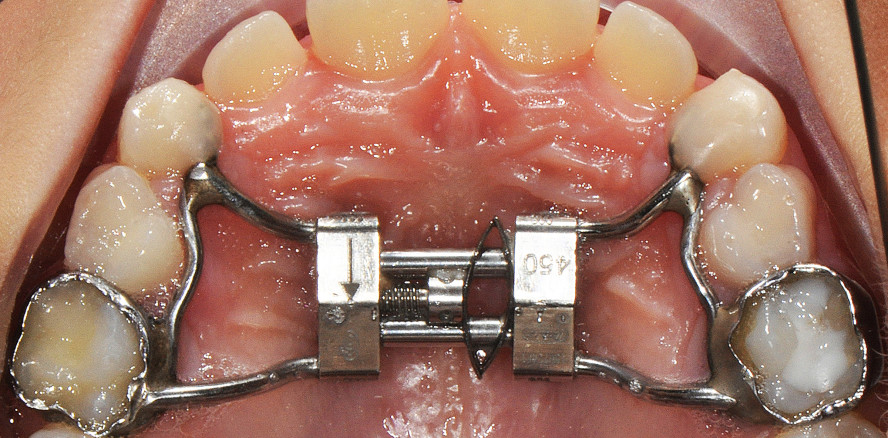

In dieser Studie wurde der Leaf Expander 6 mm/450 g als adäquat für die festgestellte Diskrepanz erachtet, entsprechend eingesetzt und an Milchzähnen verankert (Mutinelli et al. 2015).

Das Design des Leaf Expanders ist ähnlich dessen eines konventionellen Rapid Palatal Expanders. Anstelle einer Mittellinien-Jack Screw verfügt der Leaf Expander jedoch über eine Doppel-NiTi-Blattfeder, die ihre ursprüngliche Form während der Deaktivierung zurückgewinnt, woraus sich eine kalibrierte Expansion des Oberkiefers ergibt.

Der Leaf Expander wird normalerweise an den Milchzähnen verankert, wobei die oberen ersten bleibenden Molaren belassen werden, damit sie spontan expandieren können (Abb. 1a, b). Die 11 mm x 12 mm x 4 mm große Schraube kann ohne Weiteres angepasst werden, z. B. bei engem Gaumen oder bei einem Kiefer mit transversaler Defizienz. Durch Aktivierung (Komprimierung) der Feder, welche eine leichte (450 g) und konstante Kraft generiert, kann eine maximale Expansion von 6 mm erreicht werden. Um die ersten 3 mm an Expansion realisieren zu können, werden die Federblätter im Labor voraktiviert. Die Schraube wird mittels Metallligaturen oder einem speziellen Clip geblockt, welcher nach der Zementierung wieder entfernt wird. Die Reaktivierung erfolgt durch zehn Vierteldrehungen der Schraube pro Monat, bis die Expansion abgeschlossen ist (Abb. 2). Eine Vierteldrehung entspricht dabei 0,1 mm an Aktivierung. Dementsprechend generieren zehn Aktivierungen der Schraube 1 mm an Aktivierung und folglich 1 mm an Federkompression. Die maximale Anzahl an Aktivierungen beträgt 30 (für eine Expansion von insgesamt 6 mm). Eine aktive Expansion nimmt normalerweise rund fünf bis sechs Monate in Anspruch, danach sollte der Leaf Expander passiv für weitere drei Monate der Retention an Ort und Stelle belassen werden (Abb. 1, 2).